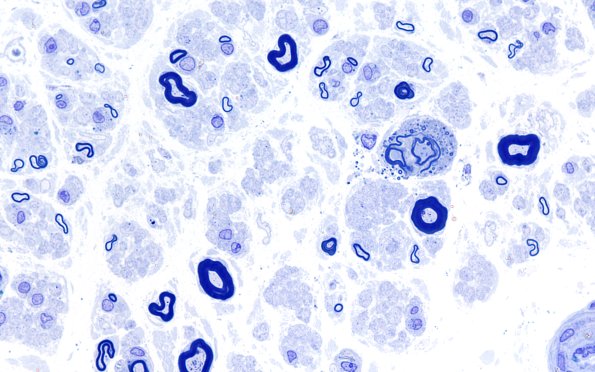

1A5 POEMS (Case 1) Plastic B 100X 11

Is this axon degenerating or demyelinating? (Plastic section)